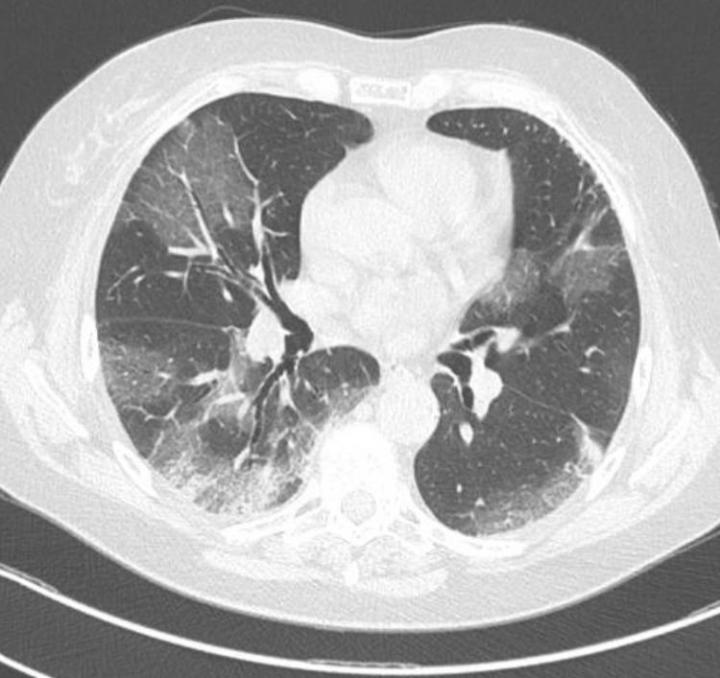

image: Thorax tomography showing pulmonary changes observed in patients with COVID19.

The clots block the lung’s small blood vessels and cause microinfarcts (cellular death or tissue necrosis). The regions of tissue that die due to a lack of blood supply are replaced by scar tissue in a process called fibrosis. In addition, microthrombi at the alveolar-blood vessel interface prevent the passage of oxygen to smaller arteries.

If the intravascular clotting is not rapidly treated, microinfarcts and fibrosis tend to spread throughout the lungs. Opportunistic bacteria and fungi may infect the damaged tissue and cause pneumonia, as SARS-CoV-2 leads to a decrease in the number of immune cells (lymphopenia). The patient may develop acute respiratory distress at the end of this process.